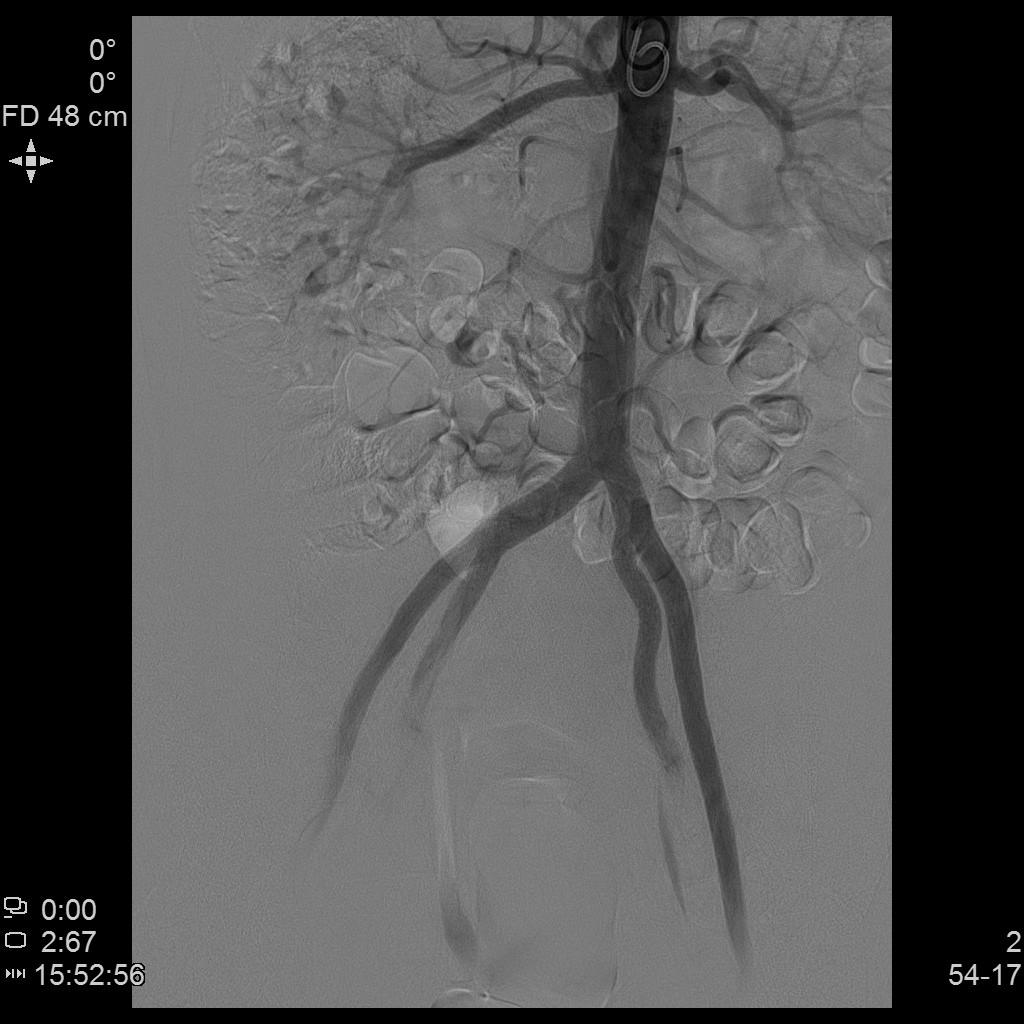

- 经桡动脉入路置入导管造影显示双侧子宫动脉明显增粗,染色丰富,子宫明显增大

- 进一步超选插管右侧子宫动脉造影确认位置

- 微导管进一步超选插管右侧子宫动脉主干造影确认位置